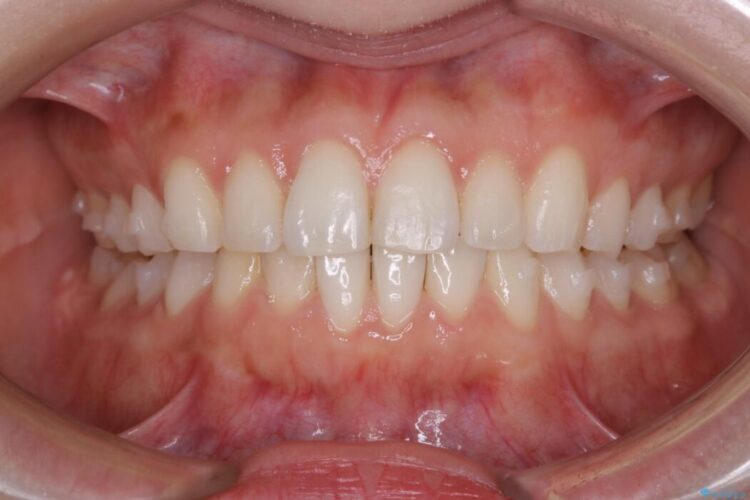

上下前歯のねじれなどで生じている歯列のガタつきをなおしたいとのことで来院されました。

半年という短期間でスピード治療が完了しました。

治療期間、治療後の出来ともに大変ご満足いただけました。

患者様の歯の状態によってはマウスピース治療でも部分矯正のように短い治療期間で歯列の矯正をすることが可能です。

治療期間・費用が共に抑えられるため、今まで矯正への一歩を踏み出せずにいた方でも満足のいく治療が受けられる場合があります。